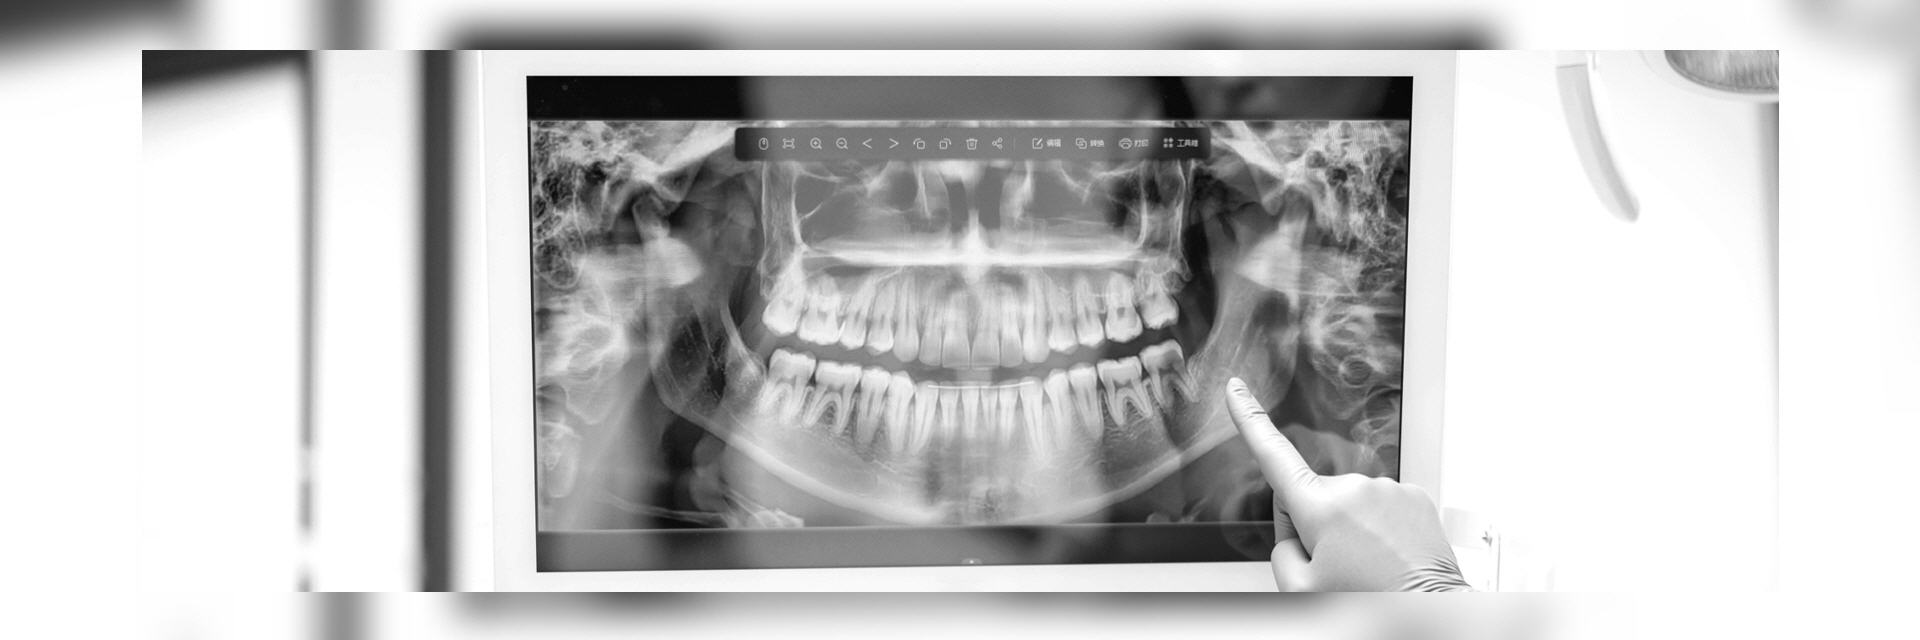

Was wir sehen können:

Im digitalen Röntgenbild sehen wir die Vorgeschichte Ihrer Zähne. Also die Spuren des Lebens, die dieses an den Zähnen hinterlassen hat. Dies betrifft Erkrankungen wie die Karies, Spalten unter Kronen oder Füllungen, Wurzelbehandlungen, Entzündungen im Knochen, aber auch Beläge und deren Auswirkungen auf den Zahnhalteapparat also den umgebenden Knochen.

Somit ergeben sich anhand des Ist-Zustands auch Rückschlüsse auf die in Zukunft zu erwartenden Probleme, die selbst im Anfangsstadium noch nicht wahrgenommen werden, sondern erst wenn zum Beispiel die Zerstörung des Zahnhalteapparats durch die Parodontitis bereits weit fortgeschritten ist.

- Orthopantomogramm (OPG) ist eine Panoramaschichtaufnahme des gesamten Ober- und Unterkiefers inkl. der Kiefergelenke in 2-dimensionaler Darstellung. Das Verfahren ist schmerzfrei, strahlenarm und auch bei Würgereiz problemlos durchführbar. Dieses Bild gibt dem Zahnarzt eine Gesamtübersicht und ermöglicht eine Beurteilung der Zahnzwischenräume, der im Knochen befindlichen Wurzeln,